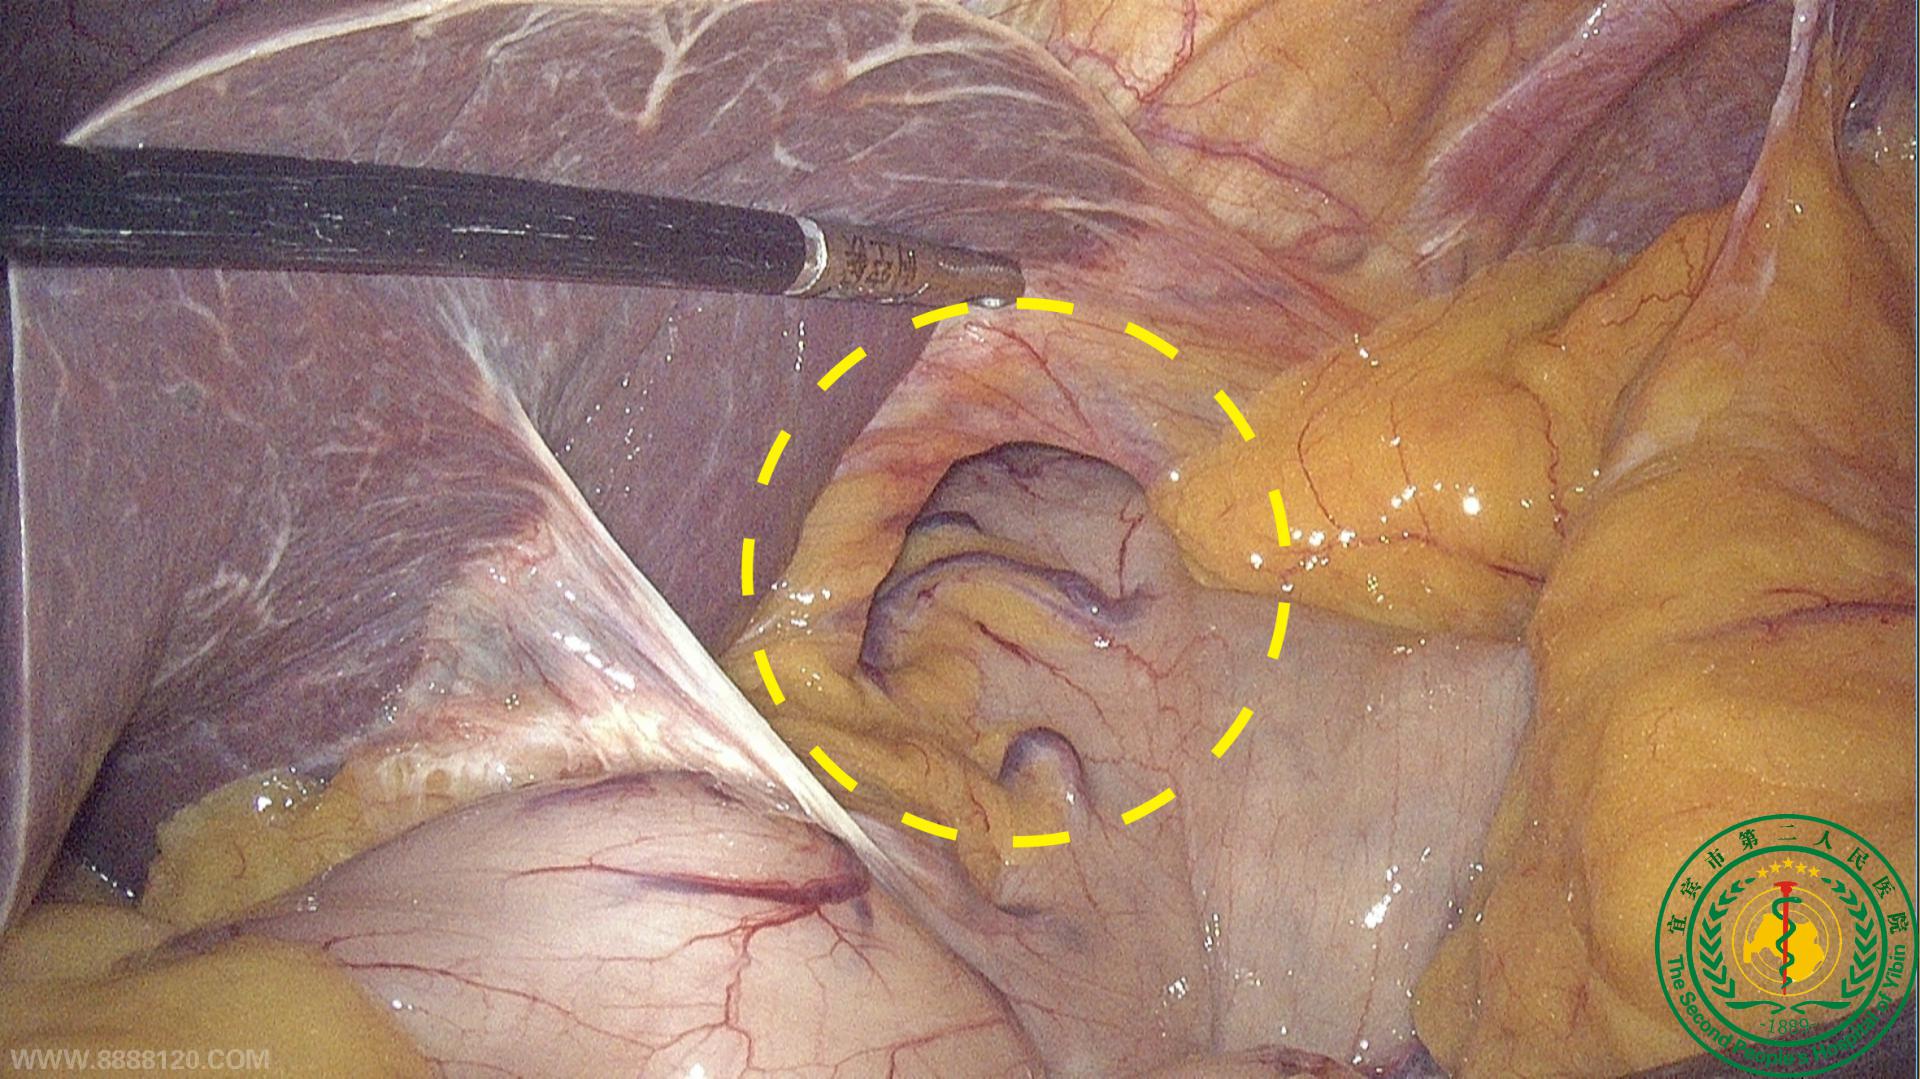

胃肠疝外科成功为一名食道裂孔疝合并双侧腹股沟疝患者手术

胃肠疝外科成功为一名食道裂孔疝合并双侧腹股沟疝患者手术19188